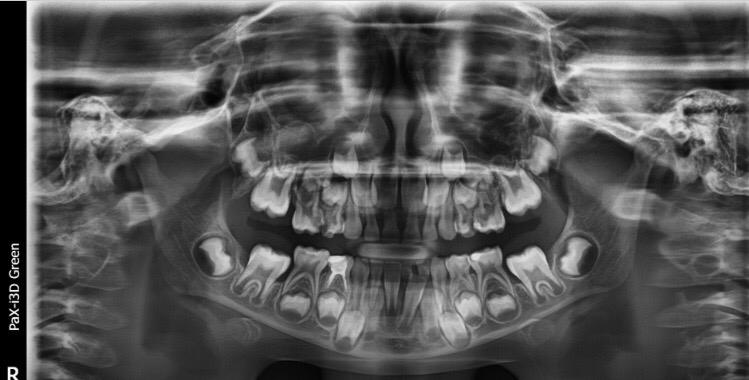

My daughter is 7 and hav deep cavity I took her to dentist one said she need 1 extraction and when I went to pediatric dentist she said she needs 4 extractions which she is going to do altogether same day I am attaching her xrays can any dentist plz advise after looking at the xrays thanks

Her both upper D are definitely for extraction and for her E need to evaluate clinically as well there might get b some Endodontic treatment and space maintainers afterwards

After extraction she will need space maintainer to keep first molar in its place so better to go for RCT to keep this tooth till age 12

can be done in two to three settings . even single extraction and space maintainers can be provided.

plan for geberal anestgesia or local anesthesia